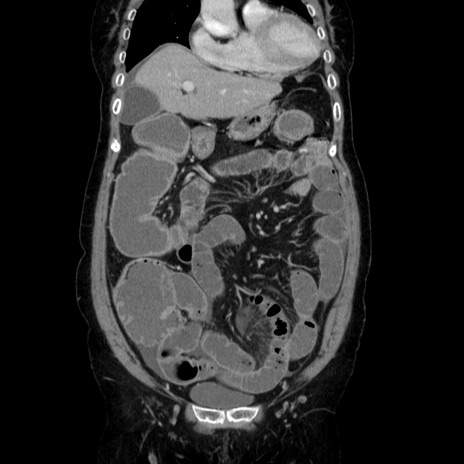

症例5(冠状断像)

【症例】70歳代女性

【主訴】お腹が張る

【現病歴】1週間くらい前から腹部膨満の自覚あり。昨日夜から増悪したため、本日救急外来受診。

【身体所見】意識清明、BT 36.5℃、BP 165/106mmHg、HR 80bpm、SpO2 98%、腹部:膨満、軟、自発痛・圧痛なし、触診にて不快感あり、腸蠕動音:減弱

【データ】WBC 12600、CRP 1.04